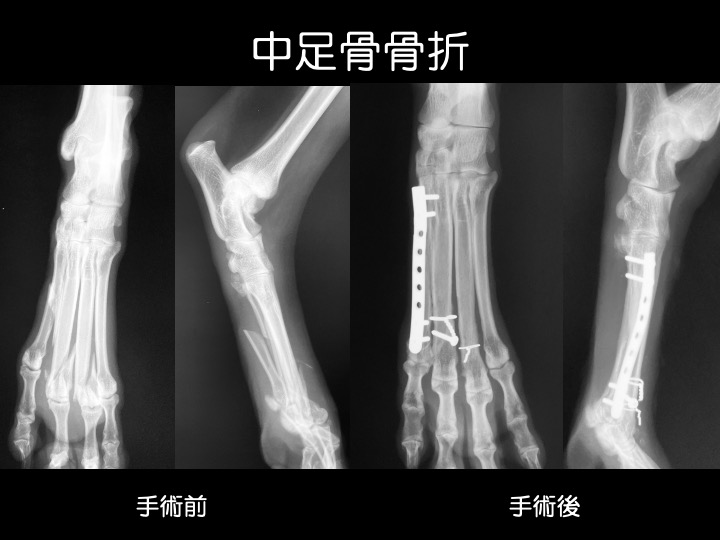

・中足骨は「足の甲」の骨で、中手骨と同様に高所からの落下や、人や車が誤って踏んでしまった場合などに折れるケースが多いようです。

・インプラントによる手術や、ギプスなどで治療することが一般的です。